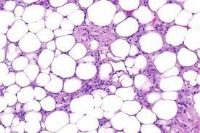

Adipose Tissue

Lipoma

Liposarcoma

Loose Connective Tissue